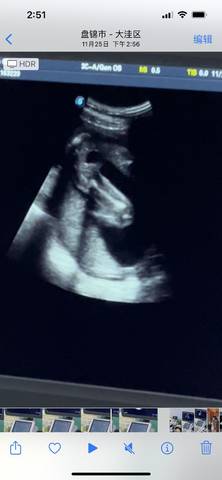

请问我这个是小男孩还是小女孩啊????有没有知道的啊 求告诉 谢谢啦

journal_insert_pic_1677719809journal_insert_pic_1677719813journal_insert_pic_1677719816

你好亲爱的,通过这个来判断男孩女孩是不太准确的哈。那么这个男孩女孩都是我们最爱的宝贝哈,我们要给他同等的关爱和呵护,也祝你可以如愿以偿,心想事成,祝你好运。

#我正在参加,超级妈妈大赛赢奖品 我猜是男宝,也要生后才能确定,宝妈也不要太在乎男女,也是你的宝宝,注意休息!

你好。我们是判断不了男宝宝跟女宝宝的,孕期定期检查,我觉得宝宝健康就好的。祝心想事成 。